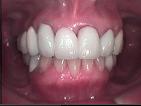

MGS(歯肉整形)

歯周炎に罹りにくくしたり、あるいは審美的要求に応えるため歯肉の整形を行うことがあります。

下のケースでは歯の形や大きさをそろえるため歯肉縁のラインを整える手術をしました。

術後